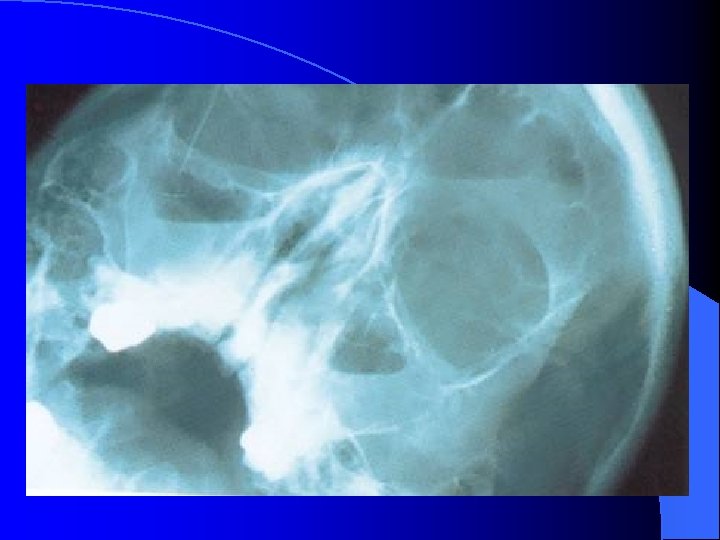

MALADIES INFECTIEUSES RHINO SINUSIENNES SINUSITE MAXILLAIRE CHRONIQUE IMAGERIE Radiographies standard Blondeau (nez-menton-plaque): CE, Niveaux hydro-aérique Panoramique dentaire: Etat bucco-dentaire, signes unilatéraux TDM crânio-faciale IRM crânio-faciale

MALADIES INFECTIEUSES RHINO SINUSIENNES SINUSITE MAXILLAIRE CHRONIQUE IMAGERIE